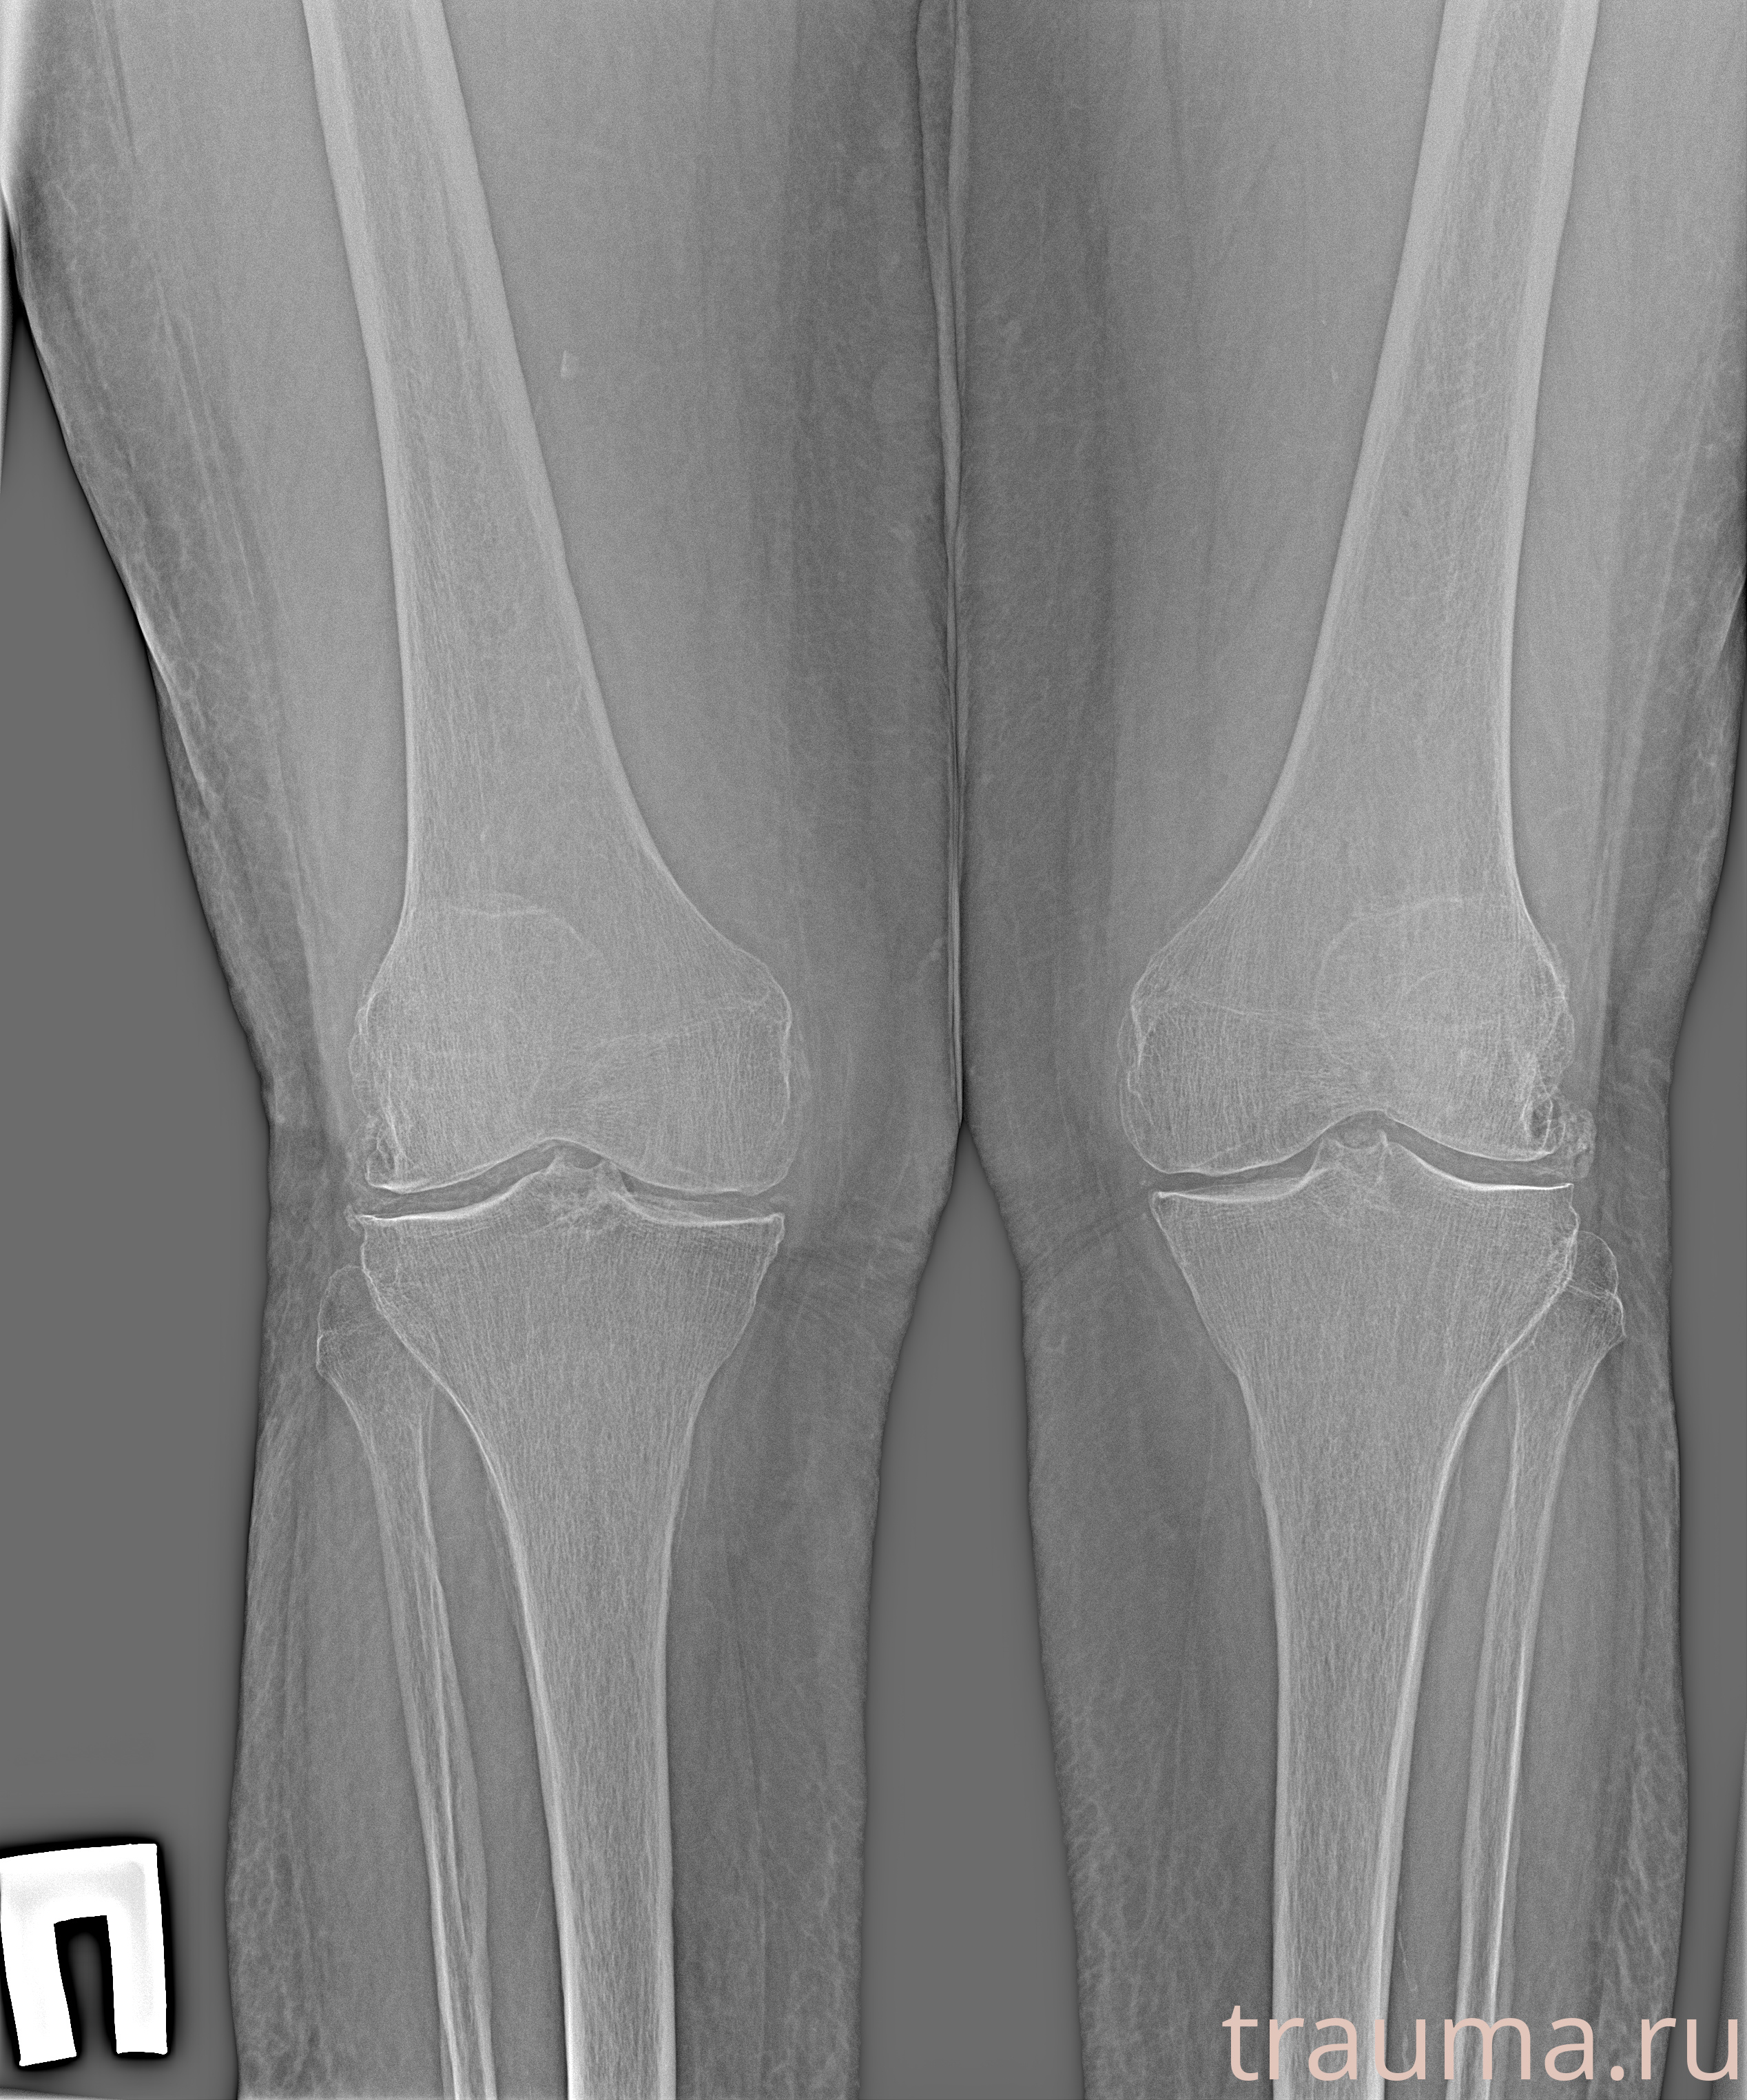

Рентгенограммы

Рентген на дому: по вашему адресу приезжает врач-рентгенолог, травматолог-ортопед с мобильным рентгеновским аппаратом, проводит диагностику травмы или заболевания, делает необходимые рентгенограммы, дает рекомендации по дальнейшему лечению. Получить качественные снимки в домашних условиях возможно благодаря уникальной методике, разработанной МосРентген Центром для института  Склифосовского